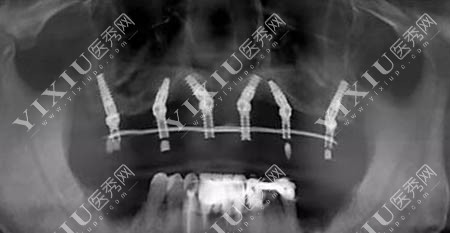

高难度种植术后ct图片

院内目前没有新手医生可以上手治疗,所有为大家服务的治疗医生都是有资质有经验的医生。